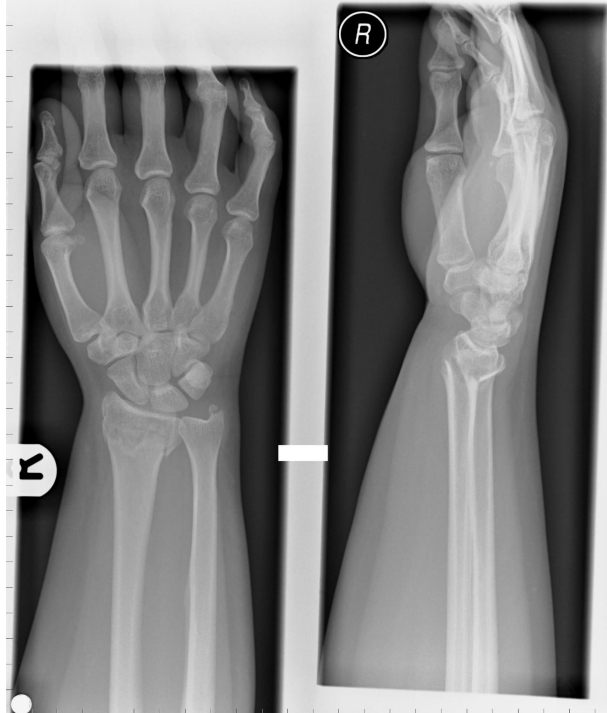

describe fracture

A

Extraarticular distal radius #

25% posterior displacement

45o dorsal angulation

Minimally displaced ulna styloid